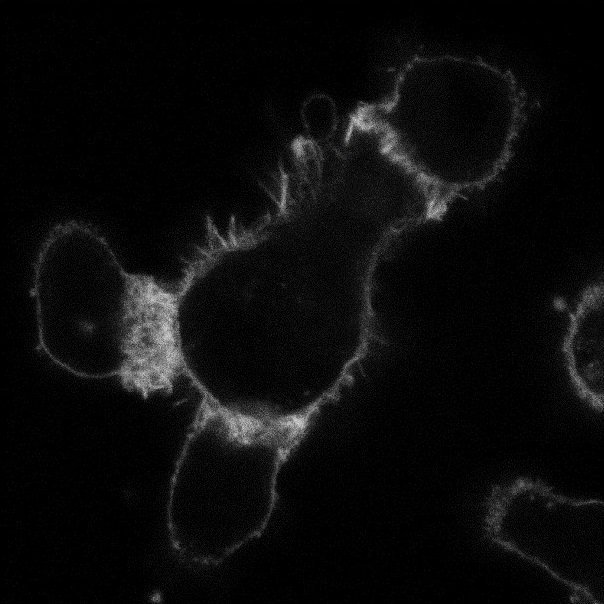

University of Bristol This green blob is a picture of Neutrophils, which are the most abundant immune cells in blood and they accumulate in a capillary at the site of an infection. Dr Borko Amulic and his lab investigates how these cells track down and destroy microbes, protecting us from infections.

<a href="/BristolUni/">University of Bristol</a> This green blob is a picture of Neutrophils, which are the most abundant immune cells in blood and they accumulate in a capillary at the site of an infection.

Dr Borko Amulic and his lab investigates how these cells track down and destroy microbes, protecting us from infections.